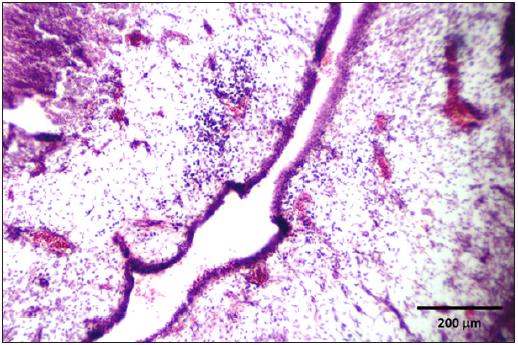

Stained slides from trachea and CAMs were screened under the light microscope. CAMs collected from cases 1 and 3 were congested, hemorrhagic and edematous (Figure 3) as compared to normal (Figure 2). The CAMs collected from cases 1 and 3 were heavily infiltrated with lymphocytes, mononuclear cells (Figure 4 & 5) and many of heterophils with congestion and haemorrhages (Figure 6 & 7). Numerous syncytial cells were also presence in CAMs with intranuclear inclusion bodies in these cells (Figure 8, 9 & 10). Some cells showed presence of intranuclear inclusion body pressing the nucleic material to the periphery of the nucleus (Figure 11). Tracheal samples showed sloughing of the mucosa of the trachea with inflammation (Figure 12) with destruction of the tracheal mucosa due to necrosis and presence of intra-nuclear inclusions within a syncytial cell (Figure 13).

Figure 3: CAM showing congestion, haemorrhages and edema.

Figure 4: CAM showing edema and infiltration of lymphocytes and mononuclear cells.

The diagnosis by histopathology is considered a valid and relatively rapid test for ILT [23]. Multinucleated cells (Syncytia) formation and intranuclear inclusion bodies are considered pathognomonic lesions for the diagnosis of ILT [24-27]. Microscopic changes vary according to the stage of the disease. Early microscopic changes in tracheal mucosa include the loss of goblet cells and infiltration of the mucosa with inflammatory cells. As the viral infection progresses, cells enlarge, lose cilia, and become edematous. Syncytial cells are formed and lymphocytes, histiocytes and plasma cells migrate into the mucosa and submucosa. Later, cell destruction and desquamation result in a mucosal surface either covered by a thin layer of basal cells or lacking any epithelial covering. Inclusion bodies are generally present for a few days at the early stage of infection before epithelial cells die [28], but they may be present for only 3-5 days after infection. In severe cases, most infected cells are detached from the tracheal lining [6]. In the current study, intranuclear inclusions were observed in tracheal epithelium along with necrosis and sloughing of the cells. These lesions were absent in some tracheal samples. This may be due to the delay of sample collection from trachea for histopathology. These kinds of lesions are observed in many other respiratory diseases, especially infectious bronchitis, avian influenza and Newcastle disease. In this way, lesions induced by ILT virus, such as hypertrophy and hyperplasia of goblet cells, are similar to those observed following infection with velogenic viscerotrope strains of Newcastle disease virus [29]. Besides, differential diagnosis might be complicated by high frequency of bacterial secondary infections. In the current study, histopathology revealed lesions of ILT in 2 out of 4 outbreaks of suspected ILT infections with suspicion of two other respiratory diseases (infectious bronchitis and Newcastle disease). However, we have not attempted to isolate and diagnose other viral pathogens that may accompany ILTV infection. Samples collected from chickens of the cases 1 and 3 had edema, hemorrhages and syncytia with intranuclear inclusion bodies associated with the chorioallantoic membrane (CAM) allowing confirmatory histopathology diagnosis. Hemorrhage may occur in cases of severe epithelial destruction and desquamation and edematous changes was observed with exposure and rupture of blood capillaries [17].